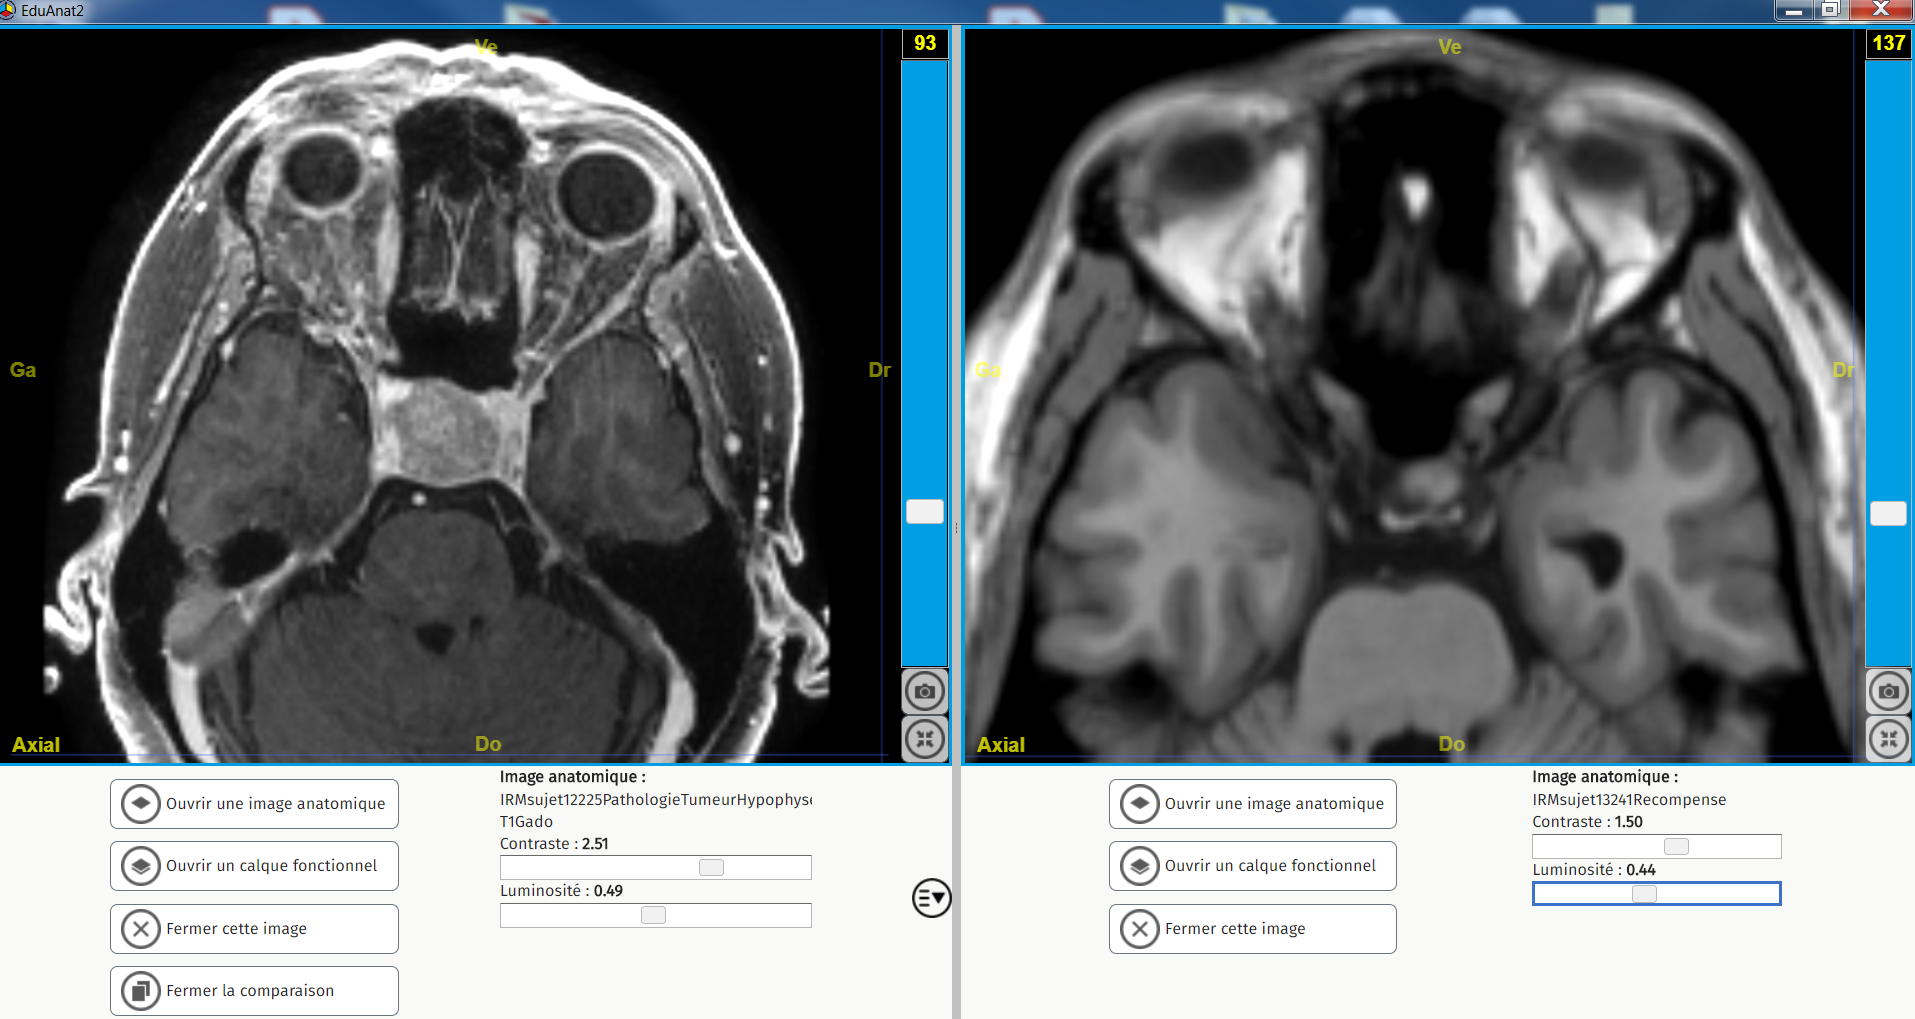

Tumeur hypophyse vision